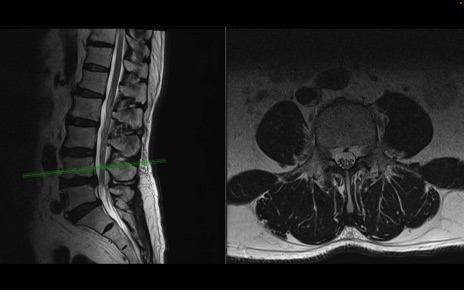

【症例】70歳代男性

【主訴】左下肢痛

【現病歴】2週間前くらいから腰痛、左下肢痛あり。左臀部から大腿、下腿外側のしびれが常時ある。歩行とともに同部位の痛みあり。

【身体所見】Lasegue70-/60+、Bragard-/±、PTR ±/±、ATR -/-、IP 5/5、TA 5/4、TS 5/5、EHL 右第1足趾なし/3、FHL 5/5、hypersthesia(-)、足背動脈触知良好

異常所見と診断は?